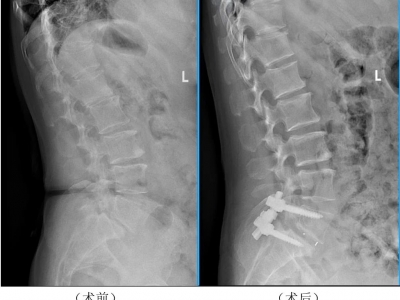

腰疼腿麻别忽视,当心腰椎滑脱!